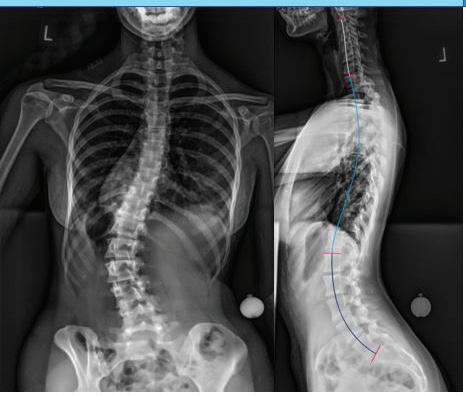

28. Cleveland Clinic. Atropine eye solution.[Internet]. Cleveland, OH: Cleveland Clinic; 2024[cited 2024 Nov 17]. Available from https://my.clevelandclinic. org/health/drugs/20729-atropine-eye-solution

29. Mayo Clinic. Neomycin, polymyxin b, and dexamethasone (opthalmic route). [Internet]. Rochester, MN: Mayo Clinic; 2024[cited 2024 Nov 17]. Available from https://www.mayoclinic.org/ drugs-supplements/neomycin-polymyxin-b-anddexamethasone-ophthalmic-route/description/ drg-20406312#

30. Im K, Mareninov S, Diaz MFP, Yong WH. An introduction to performing immunofluorescence staining. Methods Mol Biol. 2019:1897:299-311

31. Cross N, Steen CC, Zegaoui Y, Satherley A, Angelillo L. Current and future treatment of retinitis pigmentosa. Clin Opthalmol. 2020; 16:2909-2921

32. Musarella MA, Macdonald IM. Current concepts in the treatment of retinitis pigmentosa. J Opthalmol 2011:2011:753547

33. Hamel C. Retinitis pigmentosa. Orphanet J Rare Dis. 2006;1:40